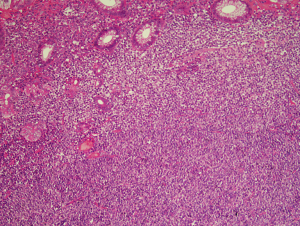

MALT lymphoma cells are initially located in the region of the peri-follicular marginal zone. This infiltrate expands to occupy the surrounding tissue to efface the surrounding stroma. While residual remnants of the acquired lymphoid tissue are usually present in the form of all or parts of reactive germinal centres in established MALT lymphoma these are frequently overrun.

The neoplastic cells of MALT lymphoma have a variable morphological appearance both between cases in different cases but also within any individual lymphoma deposit. The original descriptions recognised a cell with rather scanty cytoplasm and irregular nuclei with dense chromatin and no nucleolus (1,2) (Figure 3). The resemblance of this cell type to the small cells in the germinal centre led to the use of the term centrocyte-like (CCL) cell. In addition to CCL cells the cells may resemble monocytoid B cells with more abundant pale cytoplasm, well demarcated cytoplasmic borders and round nuclei that lack nucleoli while other cells show plasmacytoid features. A degree of plasmacytic differentiation is seen in many cases but is more pronounced in approximately a third of cases although this may rise to 40% in MALT lymphomas of the ocular region (9,10). In some cases the plasma cell component may be sufficiently extreme to almost completely eclipse the small B cell component raising a differential diagnosis with plasmacytoma. Cells with Dutcher bodies may be seen and in some instances the presence of periodic acid schiff (PAS) positive IgM-type Dutcher bodies may be useful in the distinction between MALT lymphoma and plasmacytoma in aspiration cytology preparation (11). Deposition of amyloid and light chain disease has been associated with MALT lymphoma with this a more frequent occurrence in lymphomas involving the lung (12-17). Amyloid associated with MALT lymphoma is more frequently of nodular rather than systemic type and may be in a peri-tumoural location (14-16). Up to 80% of pulmonary light chain deposition disease has been associated with MALT lymphoma with 50% of these patients having associated Sjogren’s syndrome (17). Rare cases of MALT lymphoma have also been associated with crystal storing histiocytosis (18,19).

Scattered large transformed/activated B cells are a constant feature but are not seen in clusters or groups. These cells have abundant cytoplasm and large nuclei that have open chromatin with eosinophilic nucleoli. Significant clusters of large cells are not seen and if present should raise the possibility of progression to diffuse large B cell lymphoma.